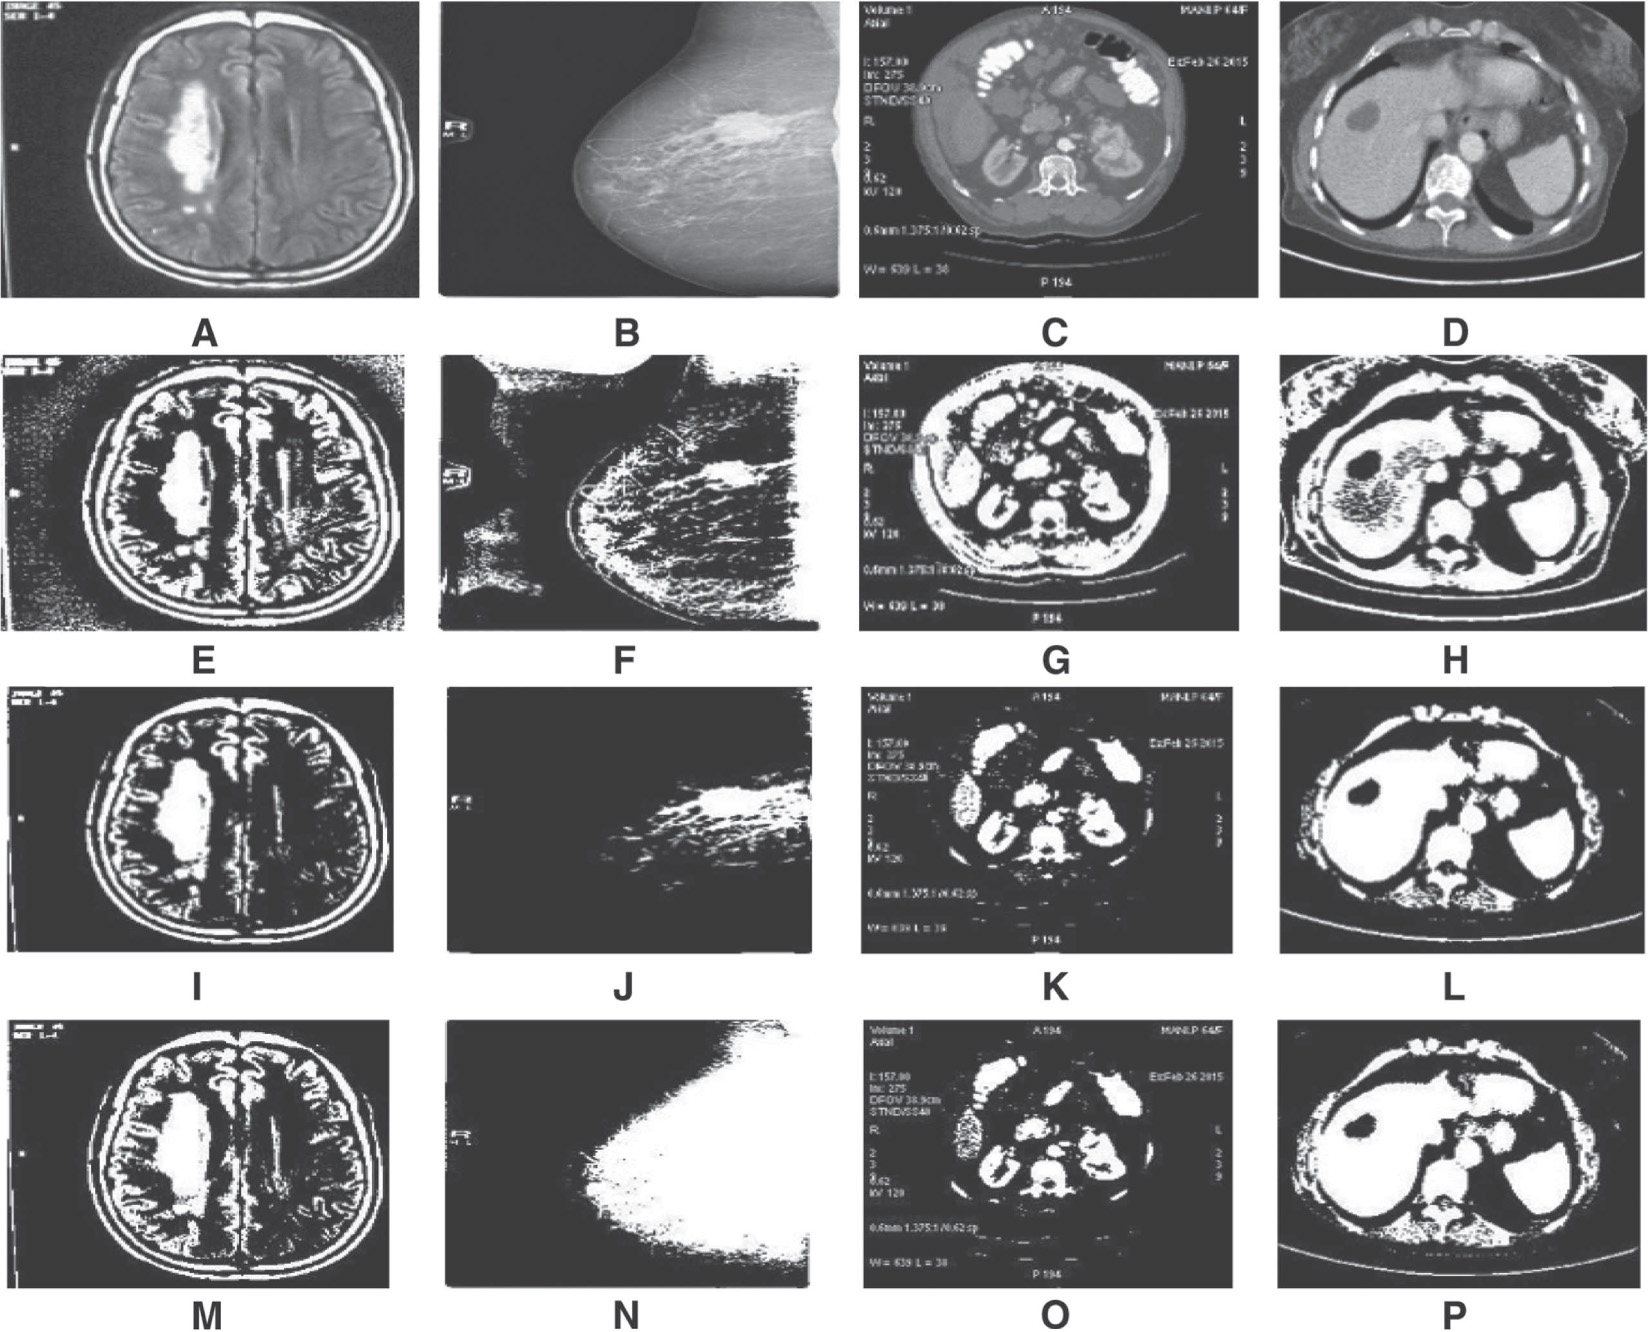

Thresholding is a basic segmentation algorithm, and the variants of thresholding algorithm are analyzed in this paper. Wellner’s adaptive thresholding results corresponding to the inputs in Figure 2A–D are depicted in Figure 2E–H, and the parameters of this algorithms are filter size, threshold value, filter type, and threshold mode. The filter type for all the inputs chosen was Gaussian, with a kernel size of 15. The maximum entropy thresholding results are depicted in Figure 2I–L. The local statistics thresholding results are depicted in Figure 2M–P.

Row 1: Input Images; Row 2: Adaptive Thresholding Output; Row 3: Maximum Entropy Thresholding Output; Row 4: Local Statistics Thresholding Output.